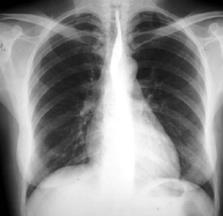

мал. 9 АЛегені

Мал. 2 А. Рентгенографія легень

Часто застосовуються у клінічній практиці і базуються на просвічуванні окремих частин тіла рентгенівськими променями за рентгенівським екраном (рентгеноскопія). На екрані можна побачити тіні різної прозорості: на фоні прозорих легень можна виявляти ділянки ущільнення легеневої тканини, визначати розміри і конфігурацію серця.

Для фіксації виявлених змін проводять рентгенографію легень (мал. 2 А) – знімають зображення на плівку, що засвічується рентгенівськими променями. На рентгенівській плівці отримують негативне зображення (світлі місця на рентгенівському екрані і навпаки темні – на плівці).